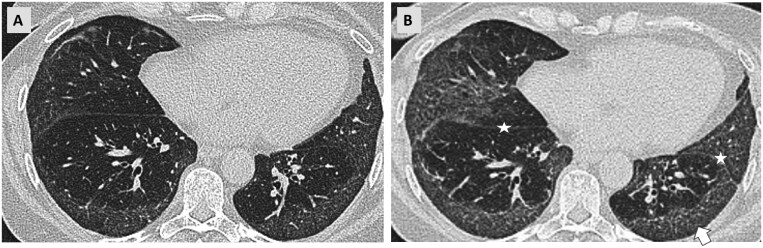

A subset of patients with interstitial lung diseases (ILDs) experiences disease progression despite standard treatment protocols. Similar to idiopathic pulmonary fibrosis, the archetype of progressive fibrotic ILDs, these patients exhibit worsening clinical symptoms, declining lung function, and progressive radiological changes, often resulting in shortened survival. This progressive disease pattern is classified under the term progressive pulmonary fibrosis or progressive fibrosing ILD. Radiological imaging, particularly high-resolution computed tomography (HRCT), is integral to diagnosing ILDs and plays a critical role within multidisciplinary ILD boards. HRCT is instrumental in identifying patients at a higher risk for disease progression and may provide valuable prognostic insights. Additionally, serial imaging is essential for detecting progression over time. While visual assessment remains the primary method for evaluating disease advancement, emerging quantitative techniques, including those utilizing machine learning, are currently undergoing validation.